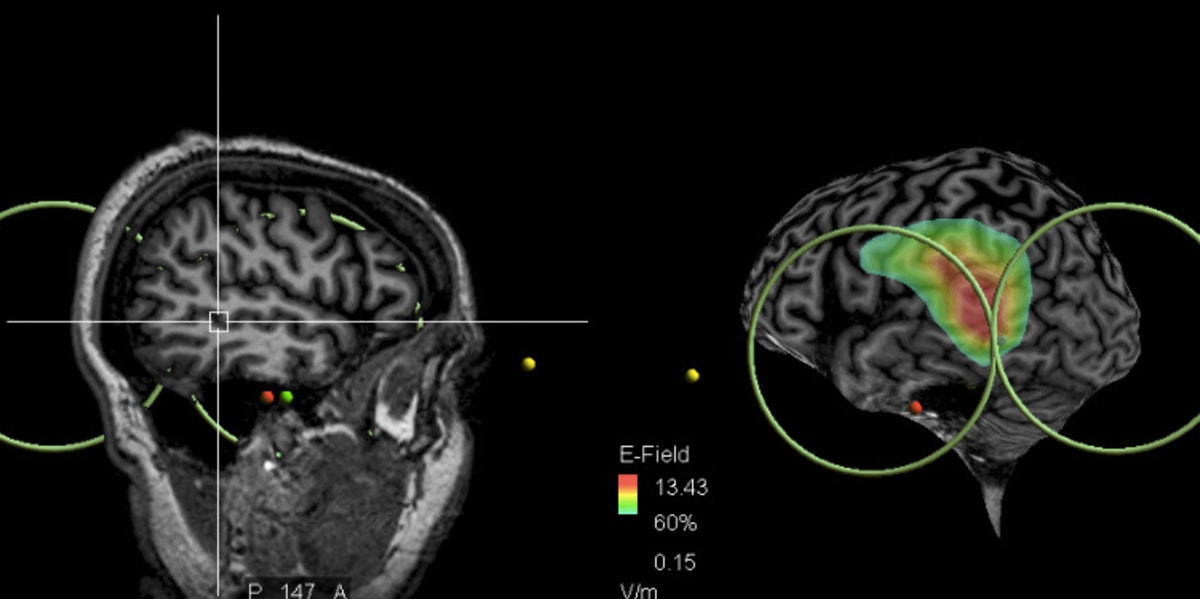

Los pacientes tratados (26) recibieron una serie de impulsos magnéticos de alta frecuencia (20 Hz) en dos sesiones por día, durante dos días. A través de imágenes de resonancia magnética (IRM), los impulsos fueron focalizados en una zona cerebral específica del lóbulo temporal asociada a la lengua. El área exacta es el cruce de la proyección de la rama ascendente de la ranura lateral izquierda y la ranura temporal superior izquierda.